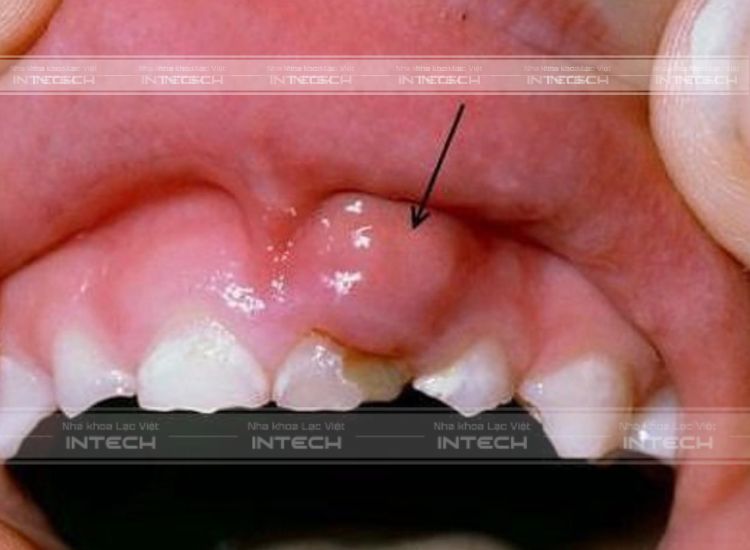

Hình thành túi mủ trên nướu răng

Đây là bệnh lý răng miệng xảy ra trong trường hợp nướu bị nhiễm trùng, gây hôi miệng, sưng và đau nhức. Các tế bào miễn dịch trong cơ thể sẽ tập trung tại vị trí lợi bị viêm để loại bỏ  các vi khuẩn gây hại. Do đó, đây là thời điểm ổ mủ hình thành nên bởi tập hợp của các xác của tế bào và vi khuẩn còn sót lại, từ đó gây ra tình trạng nhiễm trùng và sưng tấy các mô ở chân răng.

Nướu sưng đỏ

Nướu sẽ trở nên sưng to và đỏ hơn bình thường tại vị trí xung quanh vị trí bọc mủ. Khi bệnh nhân dùng tay để ấn vào các vị trí này đôi khi sẽ thấy có dịch có mùi hôi tiết ra hoặc có thể là máu.